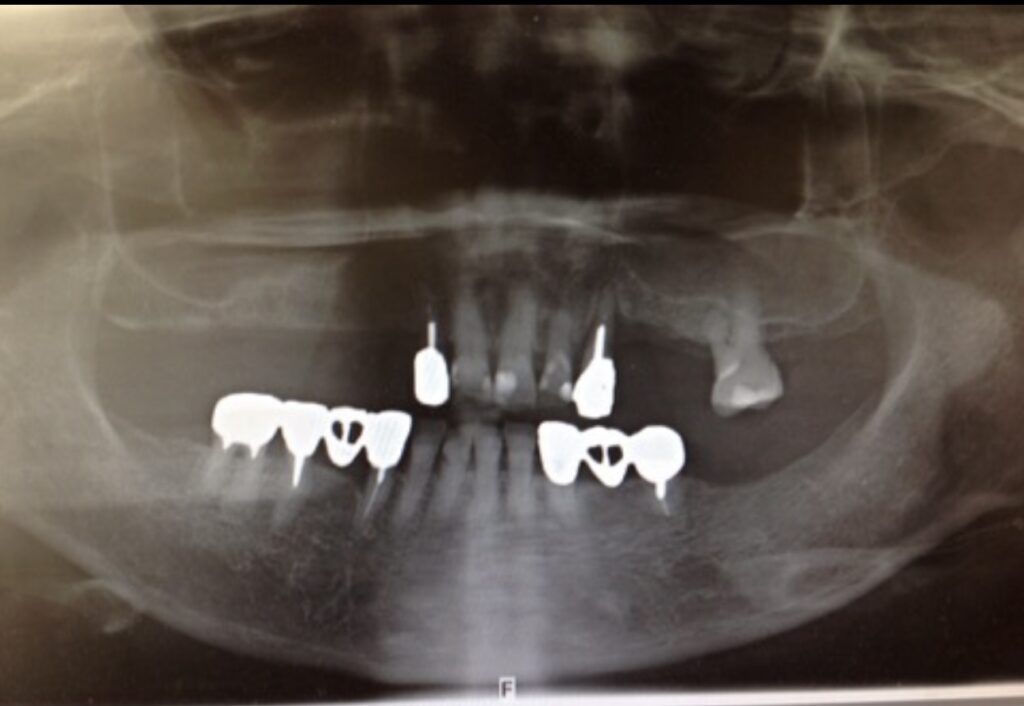

60代女性① 右上の副鼻腔(上顎洞)に骨造成した症例

他院で骨が無いのでインプラント治療はできないと言われ、長年入れ歯を使っていましたが、右上に骨をつくることで、インプラント治療でしっかり噛めるようにしました。

| 施術名 | サイナスリフト(骨造成) |

| 治療期間 | 約6ヶ月 |

| 費用 | 骨造成費 15万円(当院価格) |

| リスクや副作用 | 蓄膿症など鼻の疾患がある場合は、適さない場合がある。術直後は、痛み・腫れ・違和感・鼻出血が発生する場合がある。上顎洞に炎症が波及し、上顎洞炎を起こすことがある。 |